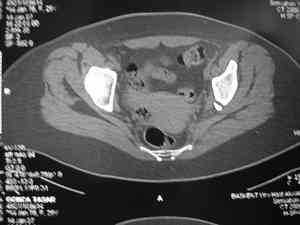

Спасибо за клинические примеры и комментарии. Если честно то просто восхищен представлеными R-ммами (классно сделали!!!). По поводу обсуждаемого больного: конечно КТ и дополнительные R-ммы сделаем. Но хочу напомнить, что после травмы прошло более 6 лет, на сегодняшний день клинически еще и R-ки признаки нестабильности эндопротеза( как бедренного компонента так и чашки). Хочется определиться как делать в аппарате или одномоментно открыто. Лично я склоняюсь к аппаратному лечению на первом этапе.

прилагаю пример с такой же давностью травмы, репонировали аппаратом